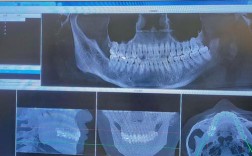

医生方案设计的合理性同样决定矫正效率,经验丰富的医生会通过X光片(全景片、头颅侧位片)、模型及口内检查,精准评估牙齿、颌骨及面部肌肉的关系,制定个性化方案,对于需要拔牙的病例,若医生未充分评估拔牙空间,可能导致牙齿排齐后仍存在间隙,需二次调整;若未使用种植钉等辅助装置进行支抗控制,可能出现前牙内收不足或后牙前移,影响矫正效果和时间,选择专业且经验丰富的医生,可最大限度优化矫正周期,避免因方案设计不当导致的延误。